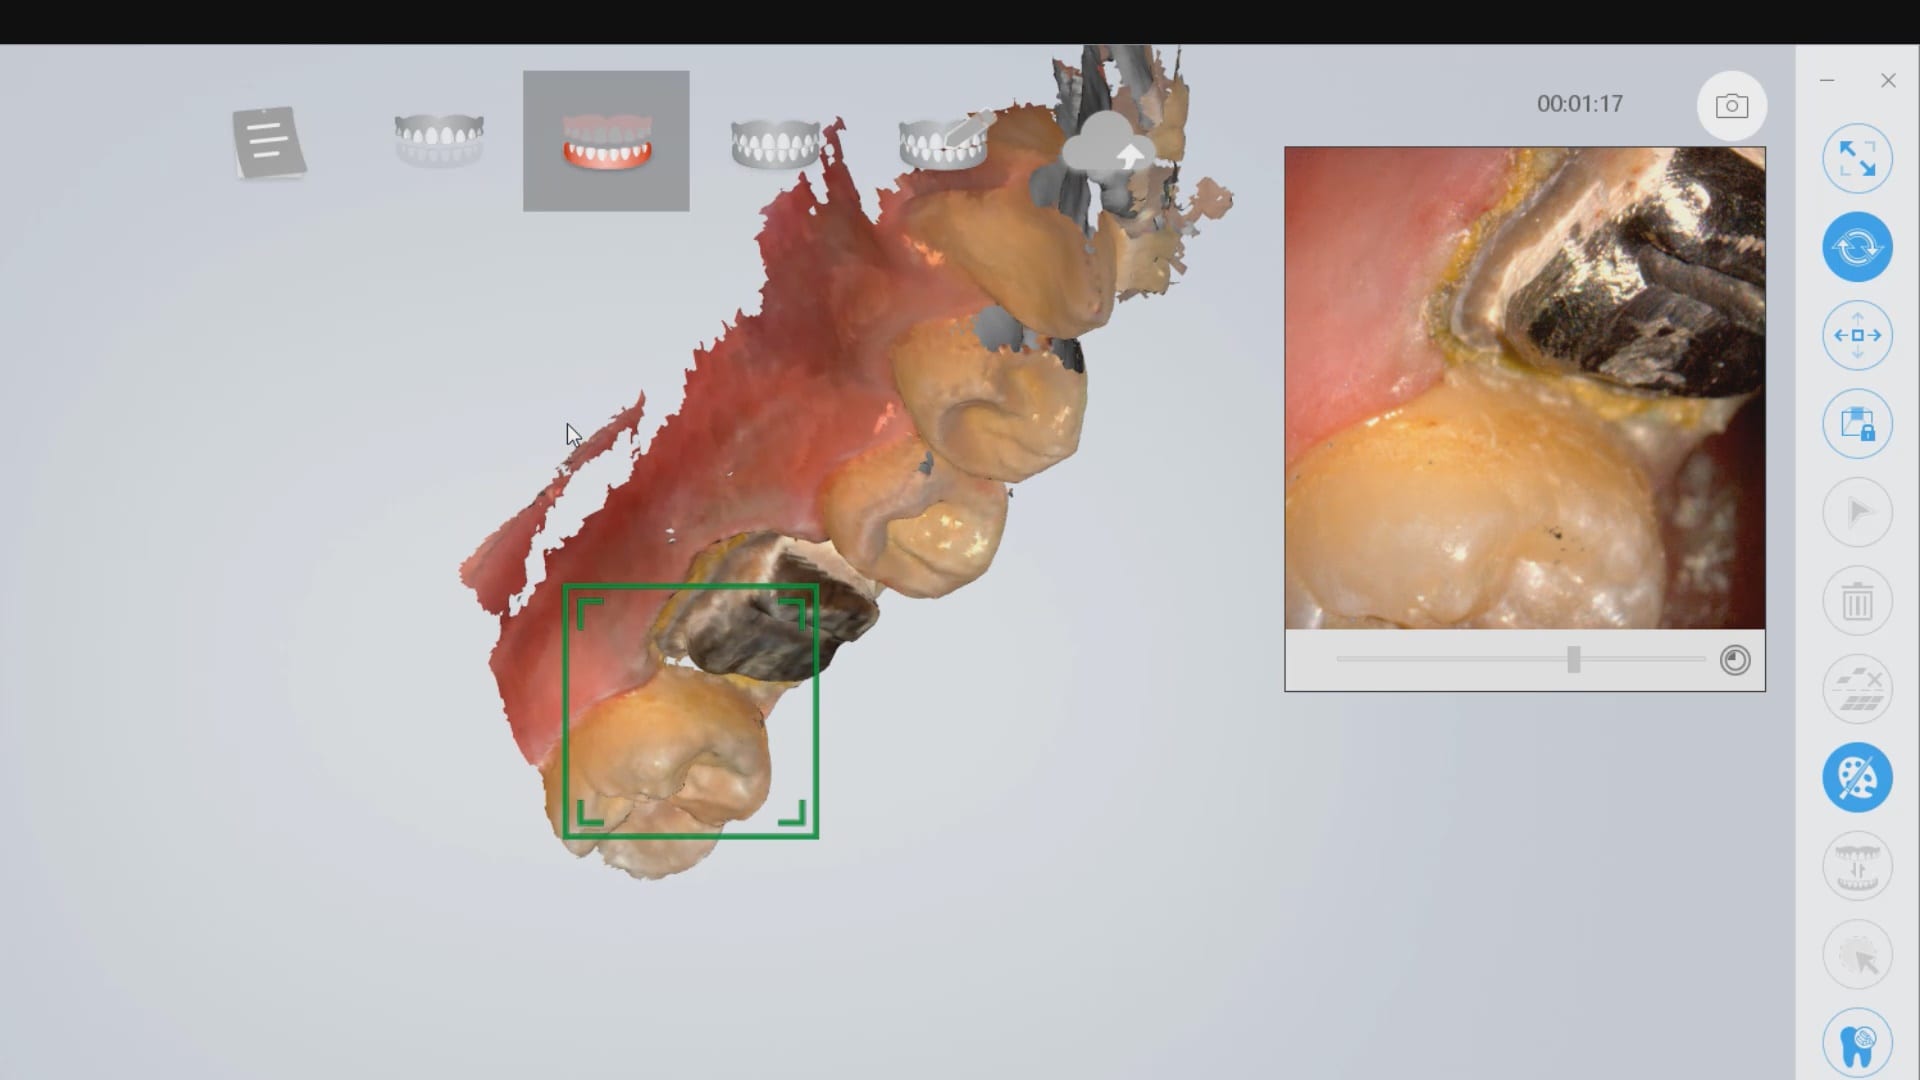

Full Arch Scan by The Shining 3D Aoralscan

March 16, 2020In this video we demonstrate how the Aoralscan can complete a full arch scan utilizing the basic principles of digital impressioning. Proper retraction, isolation, and scanning technique lead to high […]